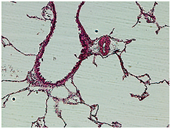

A set of twenty images is selected to assess the effectiveness of the method developed in this work. This set is divided into two groups: the first includes 10 natural scene images extracted from the Kodak dataset [43], specifically from kodim01 to kodim10 (hereinafter referred to as Natural1 to Natural10, respectively). The second group consists of 10 medical images (referred to as Medical1 to Medical10, respectively) selected from various libraries, including brain images [44,45], blood composition images (white blood cells of the basophil and eosinophil types) [46,47], X-rays [48], ocular nodules [49], dental infections [50], microphotographs of pulmonary blood vessels [51], and traumatic forearm positioning [52].

For medical images, there are instances where differences are more perceptible. For example, in the Medical3 image, the maximum contrast solution makes it difficult to visualize the internal details of the basophil (a white blood cell highlighted in the box), which could result in a less accurate interpretation. In contrast, the knee and maximum detail solutions provide a clearer view of the interior of the white blood cell. Similarly, in the Medical5 image, the maximum contrast solution highlights the hand and arm bone structures. However, the maximum detail image offers a more precise view of the internal structures within the bones (see the highlighted region), which is crucial for a more detailed evaluation. Another notable example is the Medical8 image, where the maximum detail solution offers a more detailed view of the internal structure of the eosinophil (another type of white blood cell). However, the maximum contrast image improves the visibility of red blood cells. As shown in the yellow box, this solution reveals a red blood cell that is nearly imperceptible in the other solutions. An interesting case is the Medical6 image, where only a few non-dominated solutions are present on the Pareto front. Despite the similarities among the preferred solutions, the nodules are much more perceptible in the enhanced images than in the original image, as observed in the highlighted region.